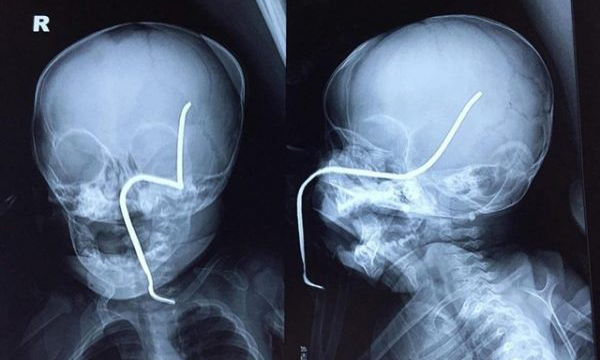

Thanh sắt dài văng trúng bé 8 tháng, xuyên thủng não

Chiếc máy cắt cỏ văng trúng thanh sắt hoen gỉ vào mặt bé gái 8 tháng tuổi gây thủng sàn sọ, xuyên qua não vùng thái dương.